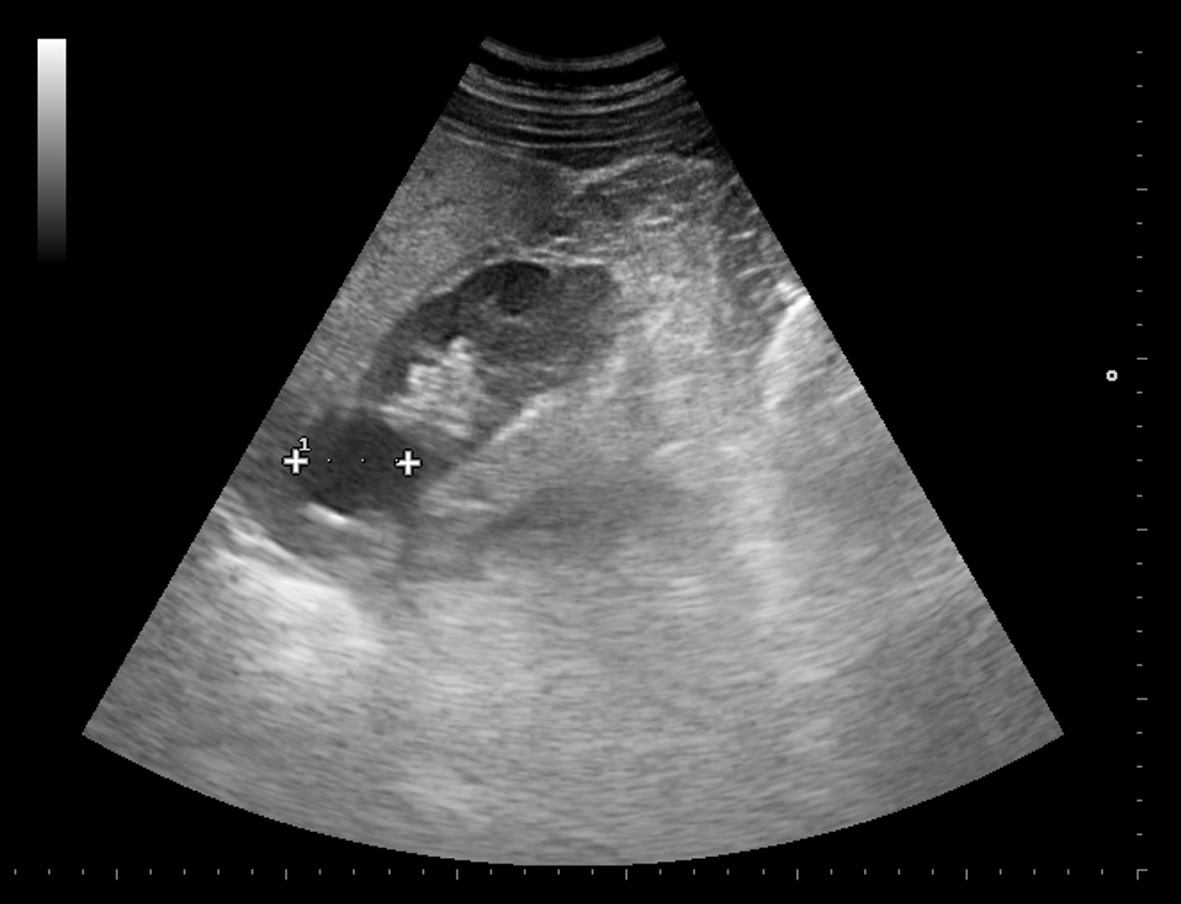

Paciente de 64 años que consulta por dolor en hipocondrio derecho de varias semanas de evolución. Se le realiza ecografía en su centro de salud donde se detecta imagen quística de 3 cm aproximadamente en riñón derecho. Se solicita TAC de abdomen para estudio de patología biliar que no se realiza por deseo del paciente.

Ecografía abdominal con vesícula biliar de paredes lisas sin imágenes en su interior, riñones simétricos con quiste renal de unos 3 cm en polo superior de riñón izquierdo sin otras lesiones o alteraciones visibles. Exploración limitada por abundante gas intestinal.

A las pocas semanas, el paciente consulta a Urgencias por hematuria macroscópica donde se le realiza una TAC y se observa masa renal izquierda dependiente de polo superior sugestiva de carcinoma renal con infiltración de ramas venosas y metástasis adrenal derecha.

Dado que fue un hallazgo accidental en un estudio de posible colelitiasis, de difícil valoración por ecografía, se solicitó TC abdominal para ampliar el estudio y poder definir bien sus características. Aparición de nueva sintomatología, hematuria, que reorienta el diagnóstico a patología renal.